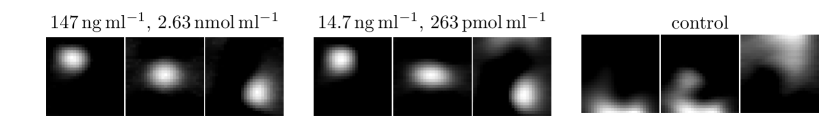

To determine the sensitivity of the imager we used a protocol developed in [4]. First, a dilution series of the tracer Perimag (micromod) was prepared with samples and varying iron mass between and . For each iron mass, the sample was moved to three different positions within the field-of-view (FOV), so that a distinction could be made between the sample signal and reconstruction artefacts. All images were recorded using a 2D imaging sequence. Results of the sensitivity study are shown in Fig. 2. It was possible to detect the sample without artefacts starting from down to . For several artefacts appeared, but the movement from the upper left to the lower right corner was still visible. For (not shown) and the control measurement, no moving sample could be observed. Therefore, the detection limit of the scanner is about iron.

To translate the iron mass into a concentration, we prepared a concentration series and used an ellipsoid (half-axes , and ) filled with different SPIO concentrations. The ellipsoid was filled with to iron in steps leading to concentrations varying between and . To determine the sensitivity limit for the concentration series we used the same experimental protocol as the iron mass study. As can be seen in Fig. 2, it was possible to detect the sample for concentrations starting at down to . For (not shown) and for the control experiment no movement of the sample could be detected. Thus, the detection limit in terms of concentration is about (), which is the lowest iron concentration imaged by MPI so far.